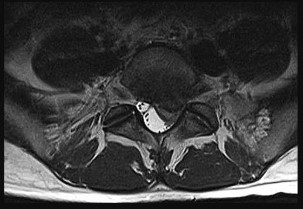

Question 3:

A 55-year-old male undergoes excision of a large cartilaginous tumor of the proximal femur. Molecular analysis of the tumor reveals a mutation in the isocitrate dehydrogenase 1 (IDH1) gene. This mutation is a hallmark of and most frequently associated with which of the following conditions?